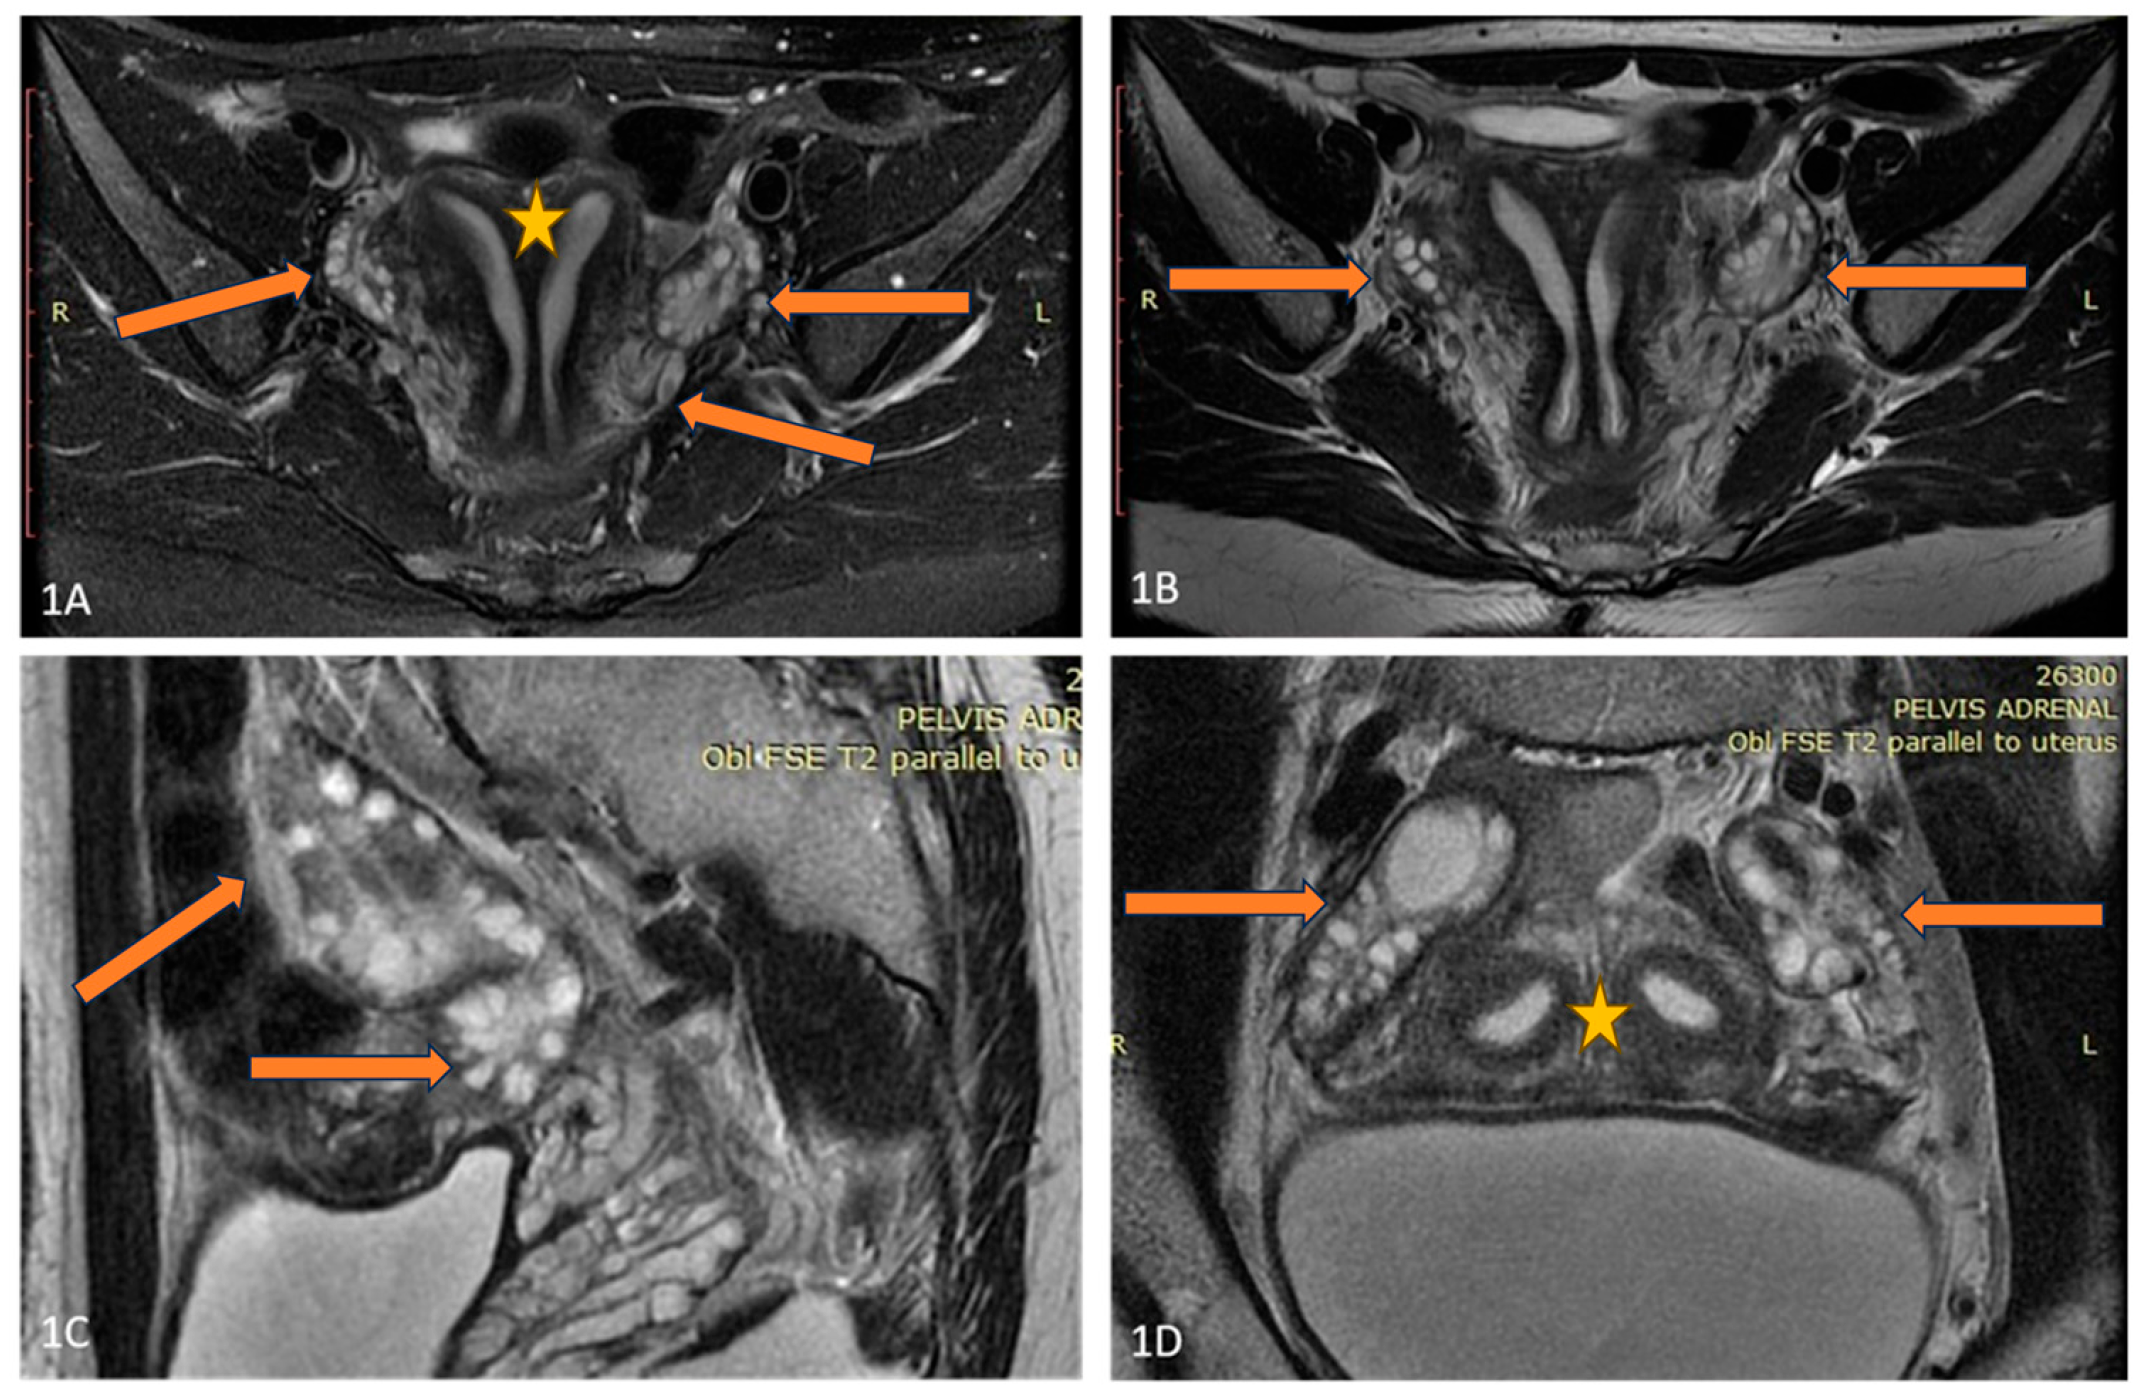

A 36-year-old lean Caucasian female patient (BMI 22.6 kg/m2) with PCOS was referred to the Endocrinology Department. The patient complained of mild hirsutism and oligomenorrhea since menarche (age 17 years). Despite chronic anovulation, she conceived spontaneously several times (two miscarriages and two live births). Increased LH and AMH levels (varying up to 50 ng/mL by unspecified analyses) as well as ultrasound evidence for polycystic ovaries were found by secondary care evaluation, and therapy with oral contraceptives was started. The patient had regular menstrual bleeding on therapy, but decided to stop the pill, leading to continuous amenorrhea, attributed to her PCOS, for several years. In 2021, the investigations in the Endocrinology Department showed normal testosterone and estradiol levels, increased LH and AMH (Table 1), as well as normal tumor markers (Ca-125, HE4). A pelvic ultrasound by an experienced gynecologist suggested 2/2 cm formation of the right ovary and no pathological findings of the left ovary. Magnetic resonance imaging (MRI) and laparoscopy were recommended because of a suspected fibroma/granulosa cell tumor, but the patient refused further investigations. Two years later, she performed the recommended MRI and a solid tumor 42/38/35 mm was described (Figure 3). She repeated her hormonal tests because of persisting amenorrhea, and again increased LH and AMH levels and normal androgens were detected (Table 1).

Figure 3. (AC) Axial T2 (A,B), and Coronal T2 (C) images of the patient demonstrate a well-circumscribed mass, representing a solid granulosa cell tumor at the level of the right ovary (blue arrow), and normal size and appearance of the left ovary (blue triangle).

The patient agreed to an operation, and a right ovariectomy was performed in the University Hospital of Obstetrics and Gynecology “Maichin dom”, Sofia, Bulgaria. A 5 cm large ovarian tumor was removed, and the histological evaluation confirmed the granulosa cell tumor—adult type. The patient was sent to an oncologist, but refused additional chemotherapy or surgery. One year after the operation, she had regular menstruation, and normal AMH and LH levels (Table 1).